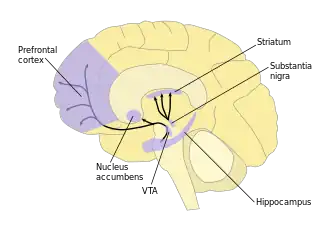

As part of the reward pathway, dopamine is manufactured in nerve cell bodies located within VTA and is released in the nucleus accumbens and the prefrontal cortex. The motor functions of dopamine are linked to a separate pathway, with cell bodies in the substantia nigra that manufacture and release dopamine into the striatum.